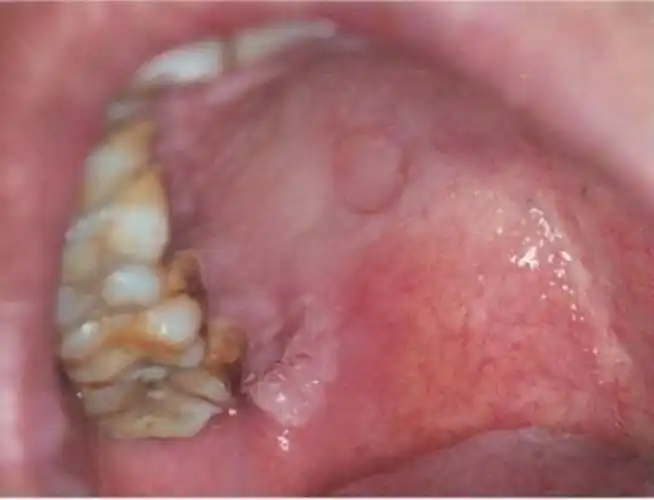

硬性下疳是感染梅毒后2-4周 或更久在接触处出现无痛性 溃疡.

梅毒感染发病初期的症状特征图片

女性梅毒急性皮损的症状